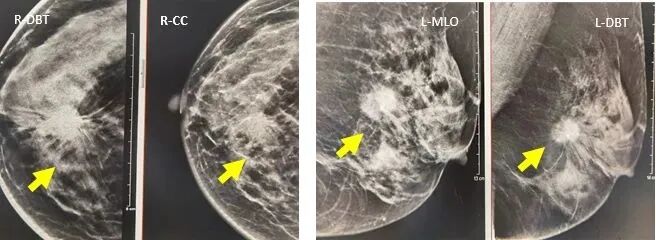

DBT与MG的对比评价

1.肿块的显示

病例1:CC,MLO/DBT显示:肿块、形态、边缘、密度、大小、内部结构显示显著优于MG。病理:乳腺粘液癌。